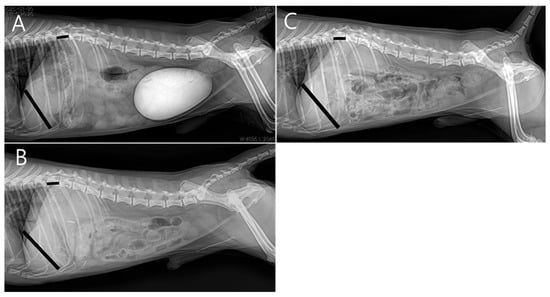

Due to poor response to medical management and the potential for disease progression, surgical intervention was elected on day 5 of hospitalization with owner consent. Preoperative CT imaging revealed a hepatic abscess measuring 1.53 × 1.43 × 1.71 cm, located on the caudomedial surface of the right medial hepatic lobe near the junction of the gallbladder and the cystic duct (Figure 3). On contrast-enhanced CT examination, the hepatic abscess and gallbladder were simultaneously visualized on transverse images. On dorsal plane CT reconstructions, the hepatic abscess was most clearly identified on one slice, while the gallbladder was visualized approximately two slices ventral to this level. Although these structures were not visible within the same dorsal plane slice, their close anatomical proximity was evident.

Figure 3.

Preoperative contrast-enhanced computed tomography (CT) images (soft tissue window; WL 100, WW 395). (A) Transverse image showing a well-defined hypoattenuating lesion adjacent to the gallbladder (arrow) with peripheral rim enhancement (arrowhead), consistent with a hepatic abscess, and surrounding fat stranding (asterisk), suggestive of localized inflammation. (B) Dorsal plane reconstruction demonstrating the hepatic abscess at its maximal extent with peripheral rim enhancement (arrowhead). Surrounding fat stranding adjacent to the lesion (asterisk), corresponding to the same region identified in subfigure A, indicates inflammatory changes in the adjacent adipose tissue. (C) A more ventral dorsal slice illustrating the gallbladder (arrow), highlighting the close anatomic proximity between the hepatic abscess and the gallbladder–cystic duct junction. Although the hepatic abscess and gallbladder are not visualized within the same dorsal plane slice, their close anatomic relationship is evident across adjacent sections.